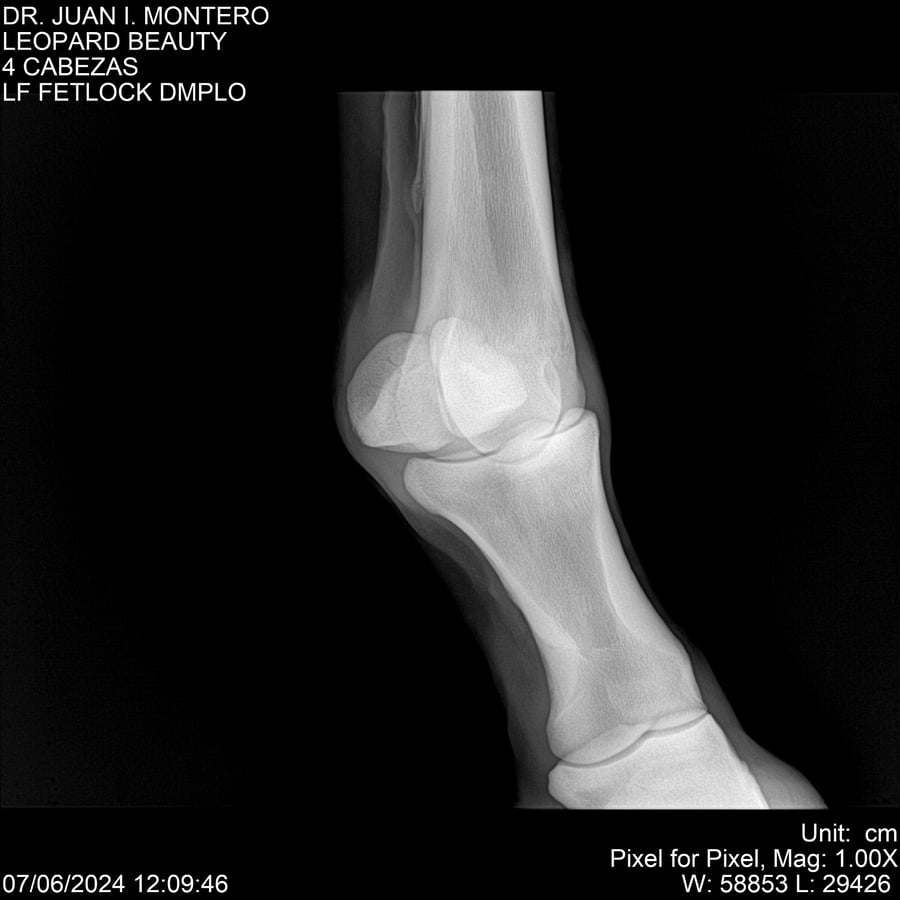

LOTE 16, LEOPARD BEAUTY Lote Anterior Volver al remate Lote Siguiente Ficha Contacto Montevideo - Ficha del Lote Identificador: #281095 Categoría: Yeguarizos Montevideo - 50 Visualizaciones ClicData Contacto Empresa: Abelenda N. R., Walter Hugo Nombre*: Teléfono* : E-mail* : Mensaje Enviar Registrese gratis Este contenido Exclusivo está disponible sólo para usuarios registrados Ingresar